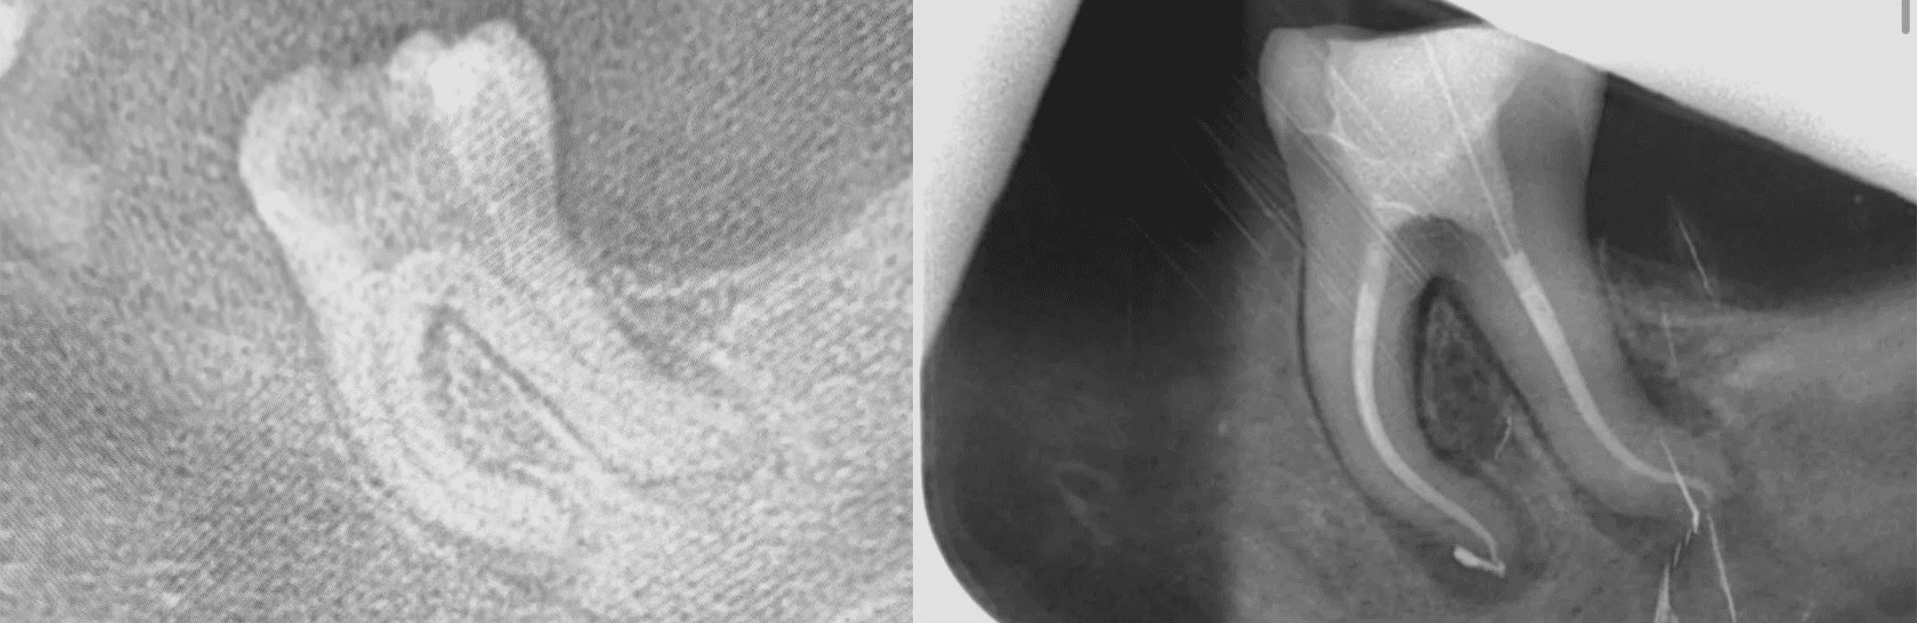

1. Accurate Diagnosis and Digital Assessment

We start with detailed diagnostics—high-resolution imaging, CBCT scans, and vitality testing. This allows us to confirm the need for root canal therapy and evaluate the tooth’s condition, both structurally and in relation to adjacent treatments.

Using modern endodontic systems and magnification, we remove infected tissue and shape the canals with precision. Irrigation and laser-assisted disinfection ensure complete removal of bacteria while preserving as much natural tooth structure as possible.